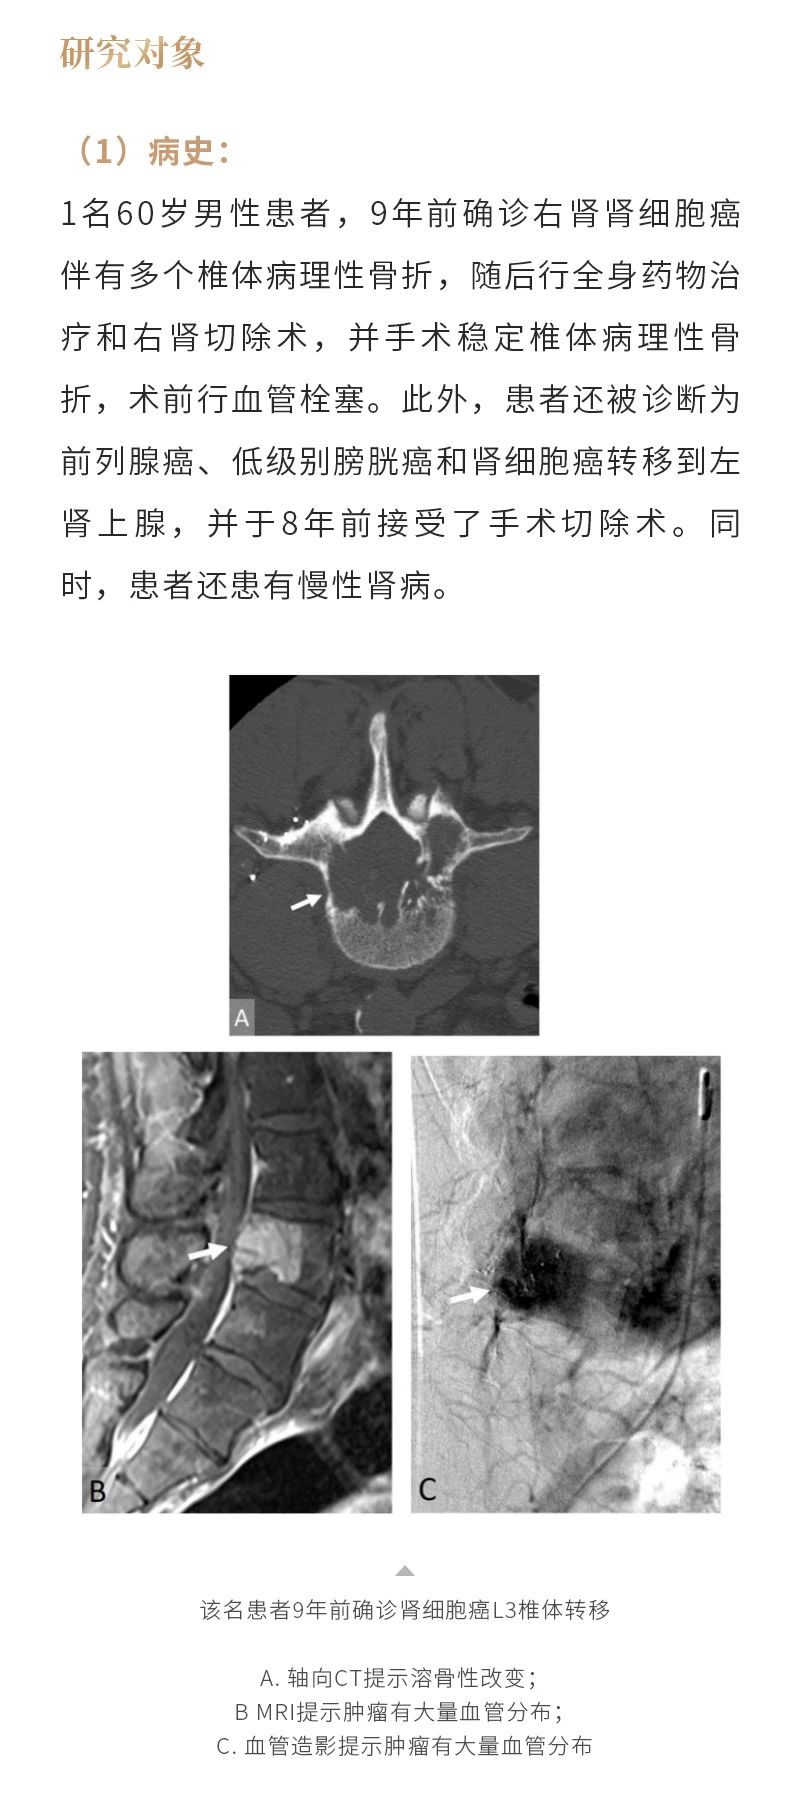

冷凍消融骨腫瘤——【海杰亞科研資訊】第285期

發(fā)布時(shí)間:2024-10-18 | 作者:海杰亞 | 瀏覽次數(shù):1127